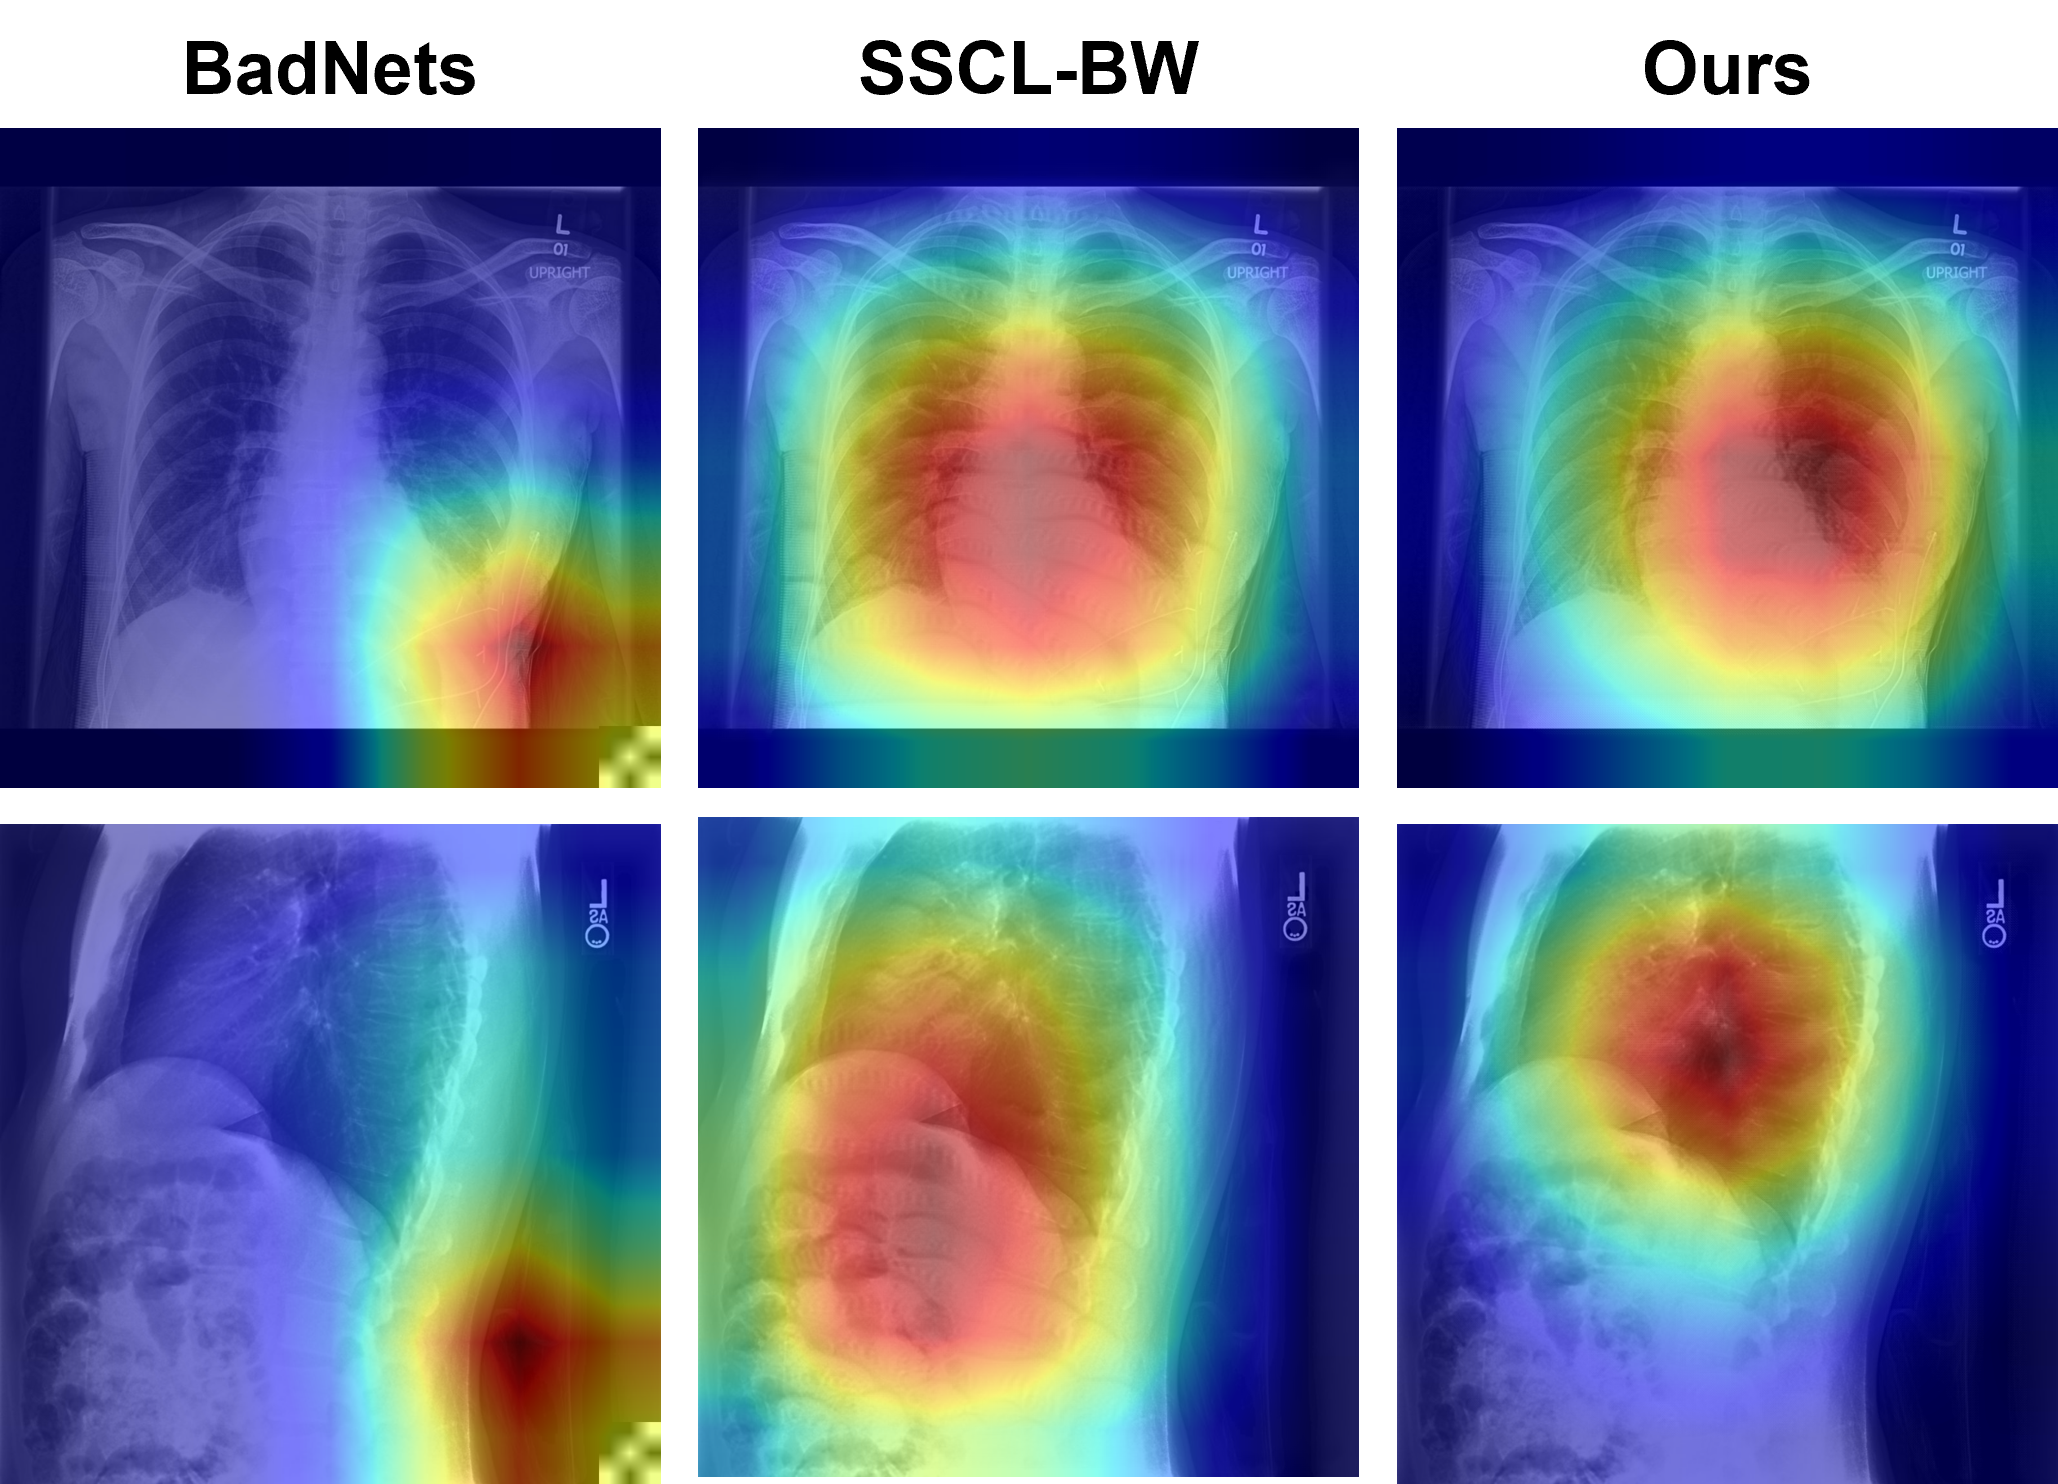

Refer to caption

Figure 3: Watermarked samples and their EigenCAM-based saliency maps from backdoored models using BadNets, SSCL-BW, and X-Mark. For BadNets, the EigenCAM mainly focuses on the trigger, while focusing on regions with the largest perturbations in SSCL-BW. In contrast, in our method, the EigenCAM focuses on the salient regions (i.e., the chest), making the backdoor difficult to detect even with automated methods.